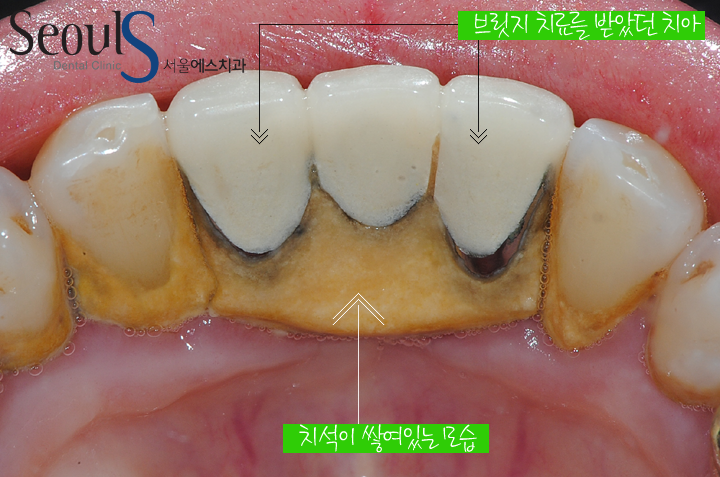

아래 앞니 모습입니다

잇몸에 염증이 진행되고 있습니다

염증의 원인은 잇몸을 누르고 있는 브릿지와 치아 뒷면에 쌓인 치석입니다

치아뒷면입니다

치석이 쌓여있습니다

아래 앞니 뒷면은 치석이 쌓이가 아주 좋은 환경으로

칫솔질을 할 때 좀 더 신경써야 합니다